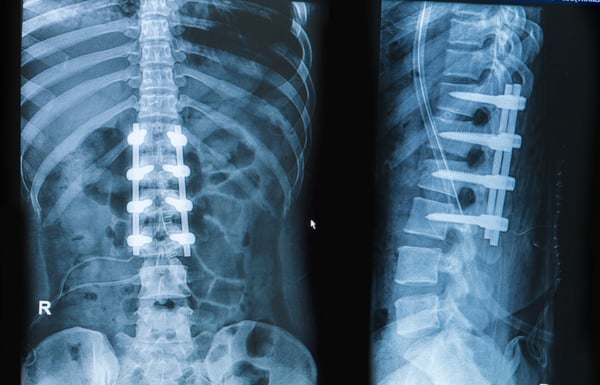

During spinal fusion, surgeons use bone grafts taken from the patient (autograft), a donor (allograft), or synthetic substitutes to promote bone growth between the vertebrae. Over time, this graft solidifies, forming a stable bone bridge. Metal implants, such as rods, plates, or screws, may also be used to hold the vertebrae in place while the bone heals.

- Implant Fixation: To hold the vertebrae in proper position during healing, the surgeon inserts titanium screws, rods, or plates. These implants provide stability, ensuring the spine remains aligned while the fusion develops.